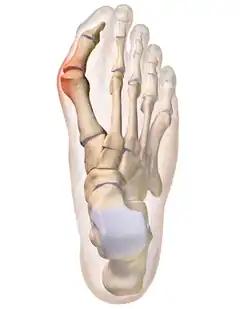

A bunion, also known as hallux valgus, is an outward deformity of the foot's metatarsophalangeal (MTP) joint which connects the big toe to the foot.[2] The rear tarsametatarsal joint that holds the metatarsal bone in a straight-ahead position weakens, the metatarsal moves outward plus rotates 90 degrees bringing the sesamoids up against the adjacent toe. This results in the head of the metatarsal bulging outward, and the big toe then bends inward toward the other toes. The joint often becomes red and painful due to rubbing in a cramped shoe.[2] The onset of bunions is typically gradual.[2] Joint complications may include bursitis or arthritis.[2] A similar condition of the little toe is referred to as a bunionette.[2]

The bump itself is due to the head of the metatarsal partly due to the swollen bursal sac or an osseous (bony) anomaly on the metatarsophalangeal joint. The larger part of the bump is a normal part of the head of the first metatarsal bone that has tilted sideways to stick out at its distal (far) end (metatarsus primus varus).

Bunions are commonly associated with a deviated position of the big toe toward the second toe, and the deviation in the angle between the first and second metatarsal bones of the foot. The small sesamoid bones found beneath the first metatarsal (which help the flexor tendon bend the big toe downwards) may also become deviated over time as the first metatarsal bone drifts away from its normal position. Osteoarthritis of the first metatarsophalangeal joint, diminished or altered range of motion, and discomfort with pressure applied to the bump or with motion of the joint, may all accompany bunion development. Atop of the first metatarsal head either medially or dorso-medially, there can also arise a bursa that when inflamed (bursitis), can be the most painful aspect of the process.